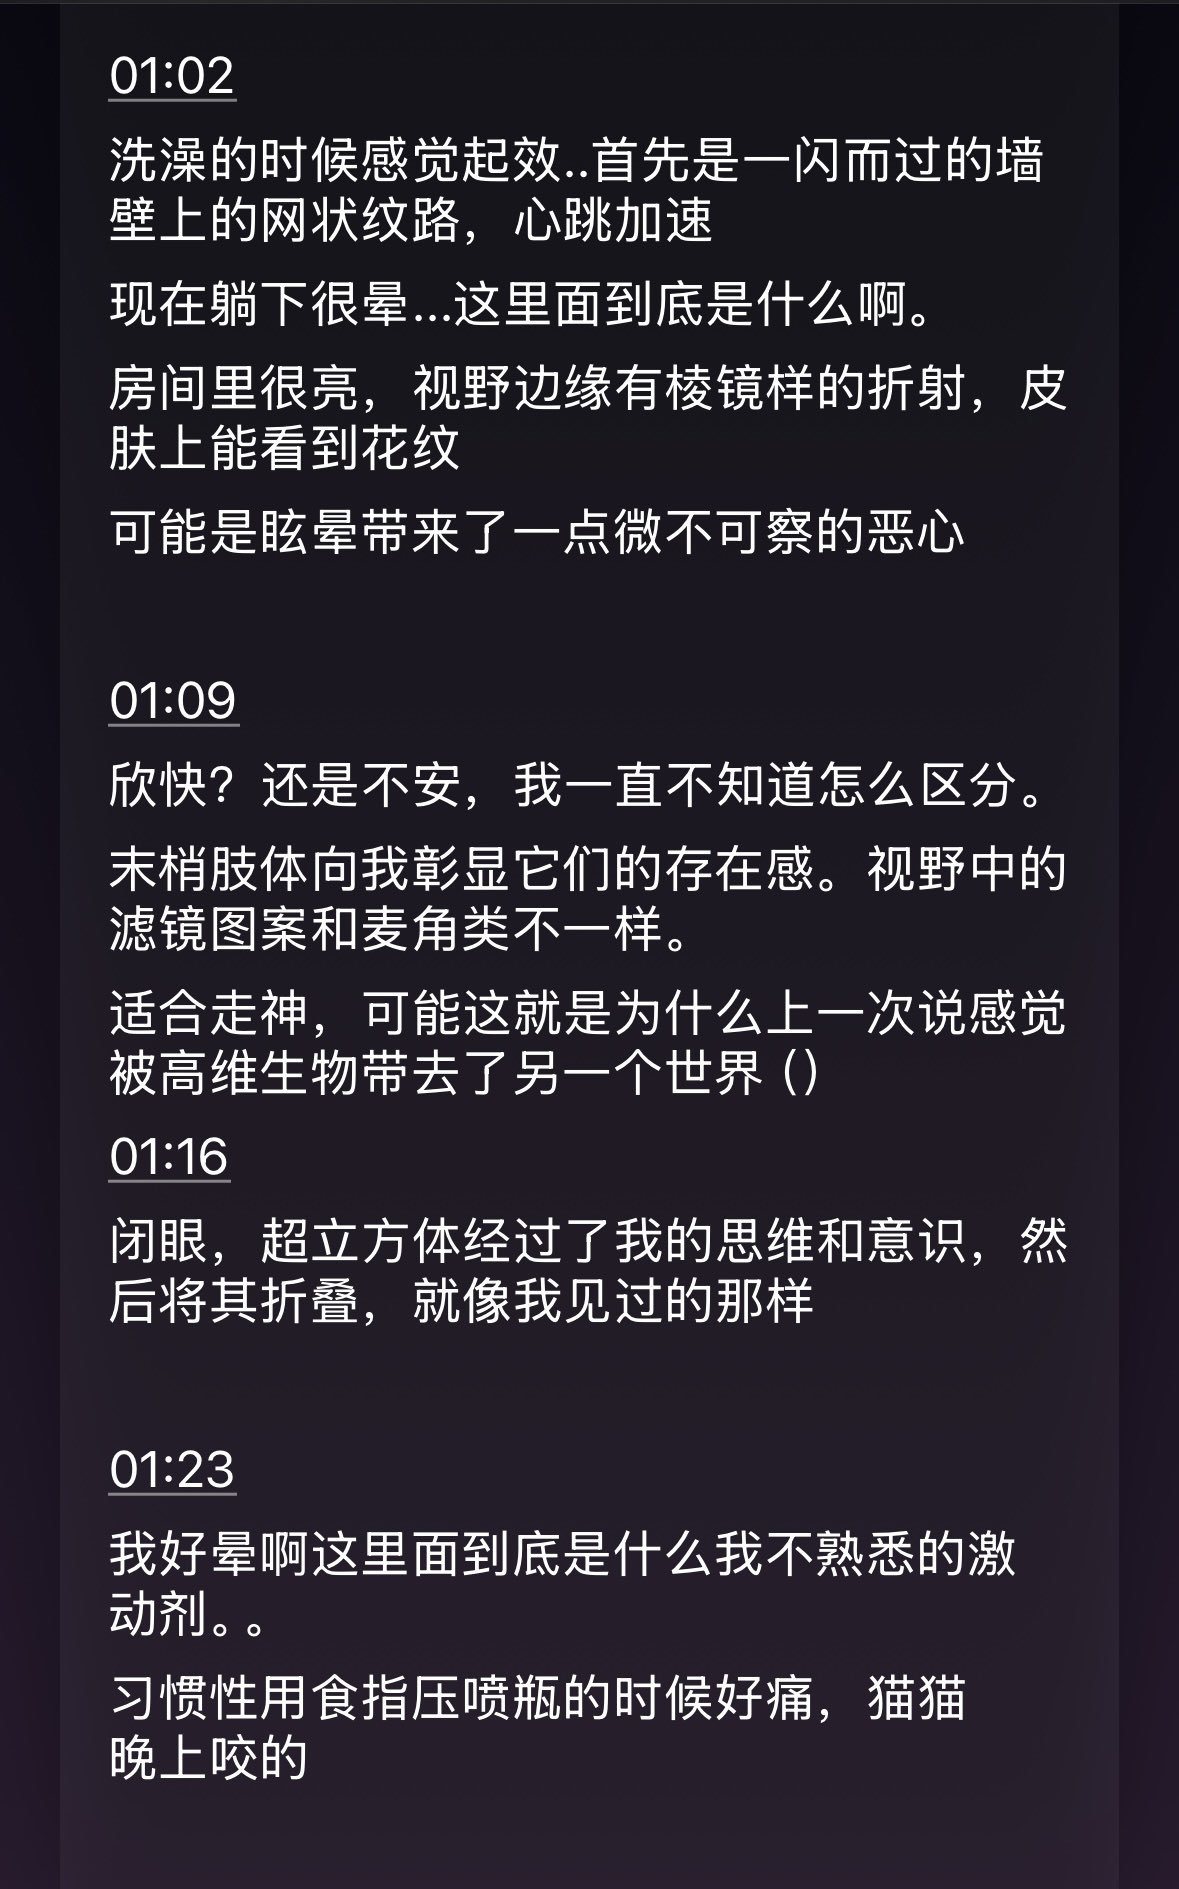

甚至在第二天有余晖的感觉,虽然发生了很多破事但没怎么影响心情*抗焦虑&镇静

运动协调性稍差,表现为走路和站立时平衡不好

此剂量下对睡眠的改善作用,增加了慢波睡眠且没有影响rem,精力恢复+

FDA数据,在临床剂量下(75-600mg)普瑞巴林的依赖性低于bzd,并相比之下它产生的认知和精神运动障碍较轻 https://t.co/TJ7ZOQ7pbC